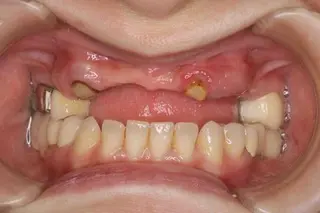

【症例1】All on Fourでインプラント埋入と固定式ブリッジを1日で装着(70代女性)

| 主訴・背景 | 下の前歯がぐらぐらして入れ歯で咬めない |

|---|---|

| 診断・治療前の状態 | 長年義歯を使用していたので下顎臼歯部歯槽骨が吸収 |

| 治療方針・計画 | 抜歯、即時インプラント埋入、即時荷重のAll on Fourで当日固定式ブリッジを装着 |

| 手術・処置内容 | ⚫︎ インプラント埋入部位32,35,42,45 インプラント4本 ⚫︎ 下顎前歯部歯槽骨骨整形、骨造成術 ⚫︎ Nobel Biocare社 ⚫︎ 歯肉付き硬質レジン歯ブリッジ |

| 治療期間・回数 | 仮歯装着まで1日、最終補綴物まで3カ月/治療回数5回 |

| 費用・料金(自費診療の場合) | 2,150,000円 |

| リスク・注意点・術後ケア | 硬質レジン歯の破折、インプラント周囲炎、定期検診 |

| 治療後の状態・経過写真 | 入れ歯による咬合時の痛みがなく、入れ歯と違ってよく咬める 8年経過良好で定期検診に6カ月毎来院 |

| まとめ・院からのコメント | 予算の関係上、人工歯に硬質レジン歯を選択したため咬耗した人工歯交換を次回定期検診時行う予定です。 |